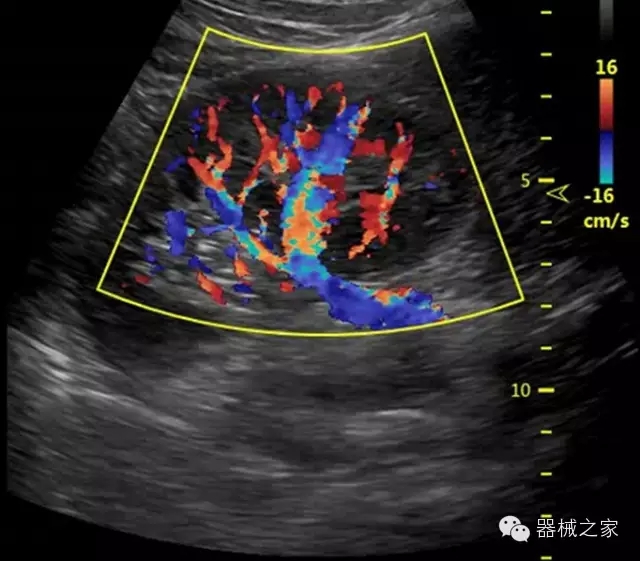

經(jīng)典產(chǎn)品:S8EXP

臨床圖片賞析

產(chǎn)品特點(diǎn)

優(yōu)異的成像技術(shù)

·亞陣元技術(shù):獨(dú)有的亞陣元技術(shù),對獨(dú)立晶片做二次切割,減少旁瓣偽像,增加臨床診斷的準(zhǔn)確性;

·μ-Scan微米成像技術(shù):開立獨(dú)有的μ-Scan技術(shù),還原出真實(shí)細(xì)膩、層次對比優(yōu)異的二維圖像;

·倒相諧波成像技術(shù):倒相諧波技術(shù)在去除基波信號的基礎(chǔ)上獲取兩倍二次諧波信號,提高組織圖像的對比分辨力;

·智能微血流成像技術(shù):智能微血流捕捉技術(shù)可以提取出隱藏在背景噪聲中的弱血流信號,大大提高低速血流的敏感性;

全面的臨床解決方案

超聲科常規(guī)領(lǐng)域應(yīng)用

·移植S40高端臺式彩超高端平臺技術(shù),滿足超聲科腹部、淺表、婦產(chǎn)科、心血管、肌骨等應(yīng)用,提供超聲科完美解決方案;

·實(shí)時的彈性成像技術(shù):提高了小器管(乳腺,甲狀腺、淺表軟組織腫瘤等)疾病鑒別診斷;

·IMT血管內(nèi)中膜自動測量:為血管性疾病評估提供了有效的評估手段;

·心功能綜合指數(shù)(TEI指數(shù)):用于左、右心室整體心臟收縮舒張功能評估的測量方法;

·全方位可調(diào)M型:有利于更好的觀察心腔大小及室壁階段性運(yùn)動的異常情況;

·組織多普勒成像(TDI):TDI可定量評價心肌運(yùn)動,判斷是否有局部病變,還可評價早期的舒張功能;

·高效3D/4D成像技術(shù):高速的4D幀頻,豐富的3D成像模式,智能斷層切片功能;

POC領(lǐng)域解決方案

·外觀小巧;

·穿刺增強(qiáng)技術(shù):可有效提高進(jìn)針區(qū)圖像分辨率,提高進(jìn)針亮度,全面提高一次性穿刺的成功率;

全面的術(shù)中探頭解決方案

·小凸探頭:開放性手術(shù),實(shí)時監(jiān)測病灶位置,提高手術(shù)成功率,可應(yīng)用于麻醉科、肝膽外科、腫瘤外科、神經(jīng)外科、泌尿外科等手術(shù);

·L型線陣探頭:高分辨率圖像,清晰顯示病灶位置,提高手術(shù)成功率,可應(yīng)用于麻醉科、胸外科、肝膽外科、腫瘤外科、神經(jīng)外科、泌尿外科等應(yīng)用;

·MPTEE:經(jīng)食道探頭術(shù)中監(jiān)測,可測量心臟前負(fù)荷(左室舒張末期大小、右房大?。?、心排血量、后負(fù)荷、收縮功能、室壁運(yùn)動分析、肝靜脈血流(與中心靜脈壓相關(guān))等,術(shù)后還能及時評估手術(shù)效果評估;

·獨(dú)有的大角度及實(shí)時溫控技術(shù),能同一切面顯示宮頸及宮體,有效減低了患者的痛苦,及保護(hù)粘膜保證了醫(yī)療安全;

高效的人機(jī)工程學(xué)設(shè)計(jì)

·15‘’高清醫(yī)用顯示器;

·內(nèi)置雙探頭接口;

·可升降臺車,1拖3探頭擴(kuò)展器;

·m-Tuning一鍵優(yōu)化;

CFDA注冊證編號

·粵食藥監(jiān)械(準(zhǔn))字20132230491